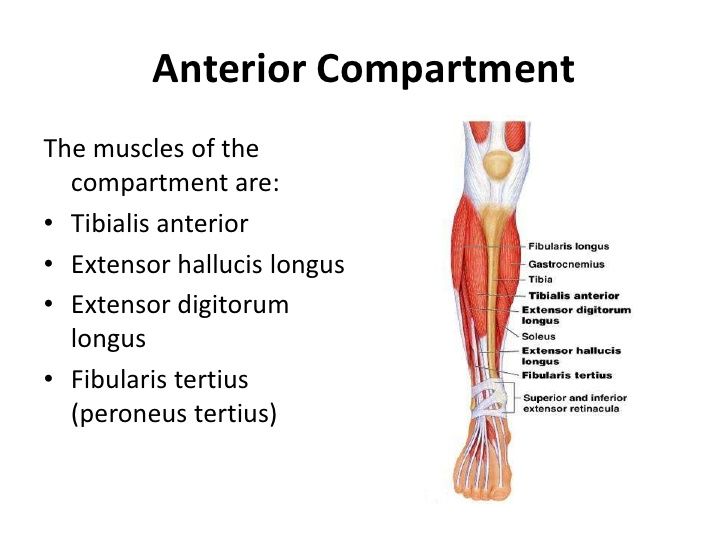

what are the 4 muscular compartments?

anterior

what muscles are on the anterior compartment?

anterior tibialis

extensor hallucis long

extensor digitorum long

peroneus tertius

what nerves are on the anterior compartment?

deep peroneal nerve

anterior tibial artery